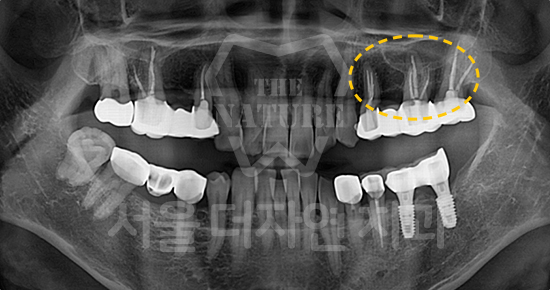

Even patients with highly complex surgical conditions are not turned away. Based on extensive experience in advanced implant cases, we provide the most appropriate implant solutions.

-

Implant Revision Referral Clinic

Using advanced equipment and extensive clinical expertise, our specialists identify the exact cause of implant failure and provide precise solutions through detailed analysis.